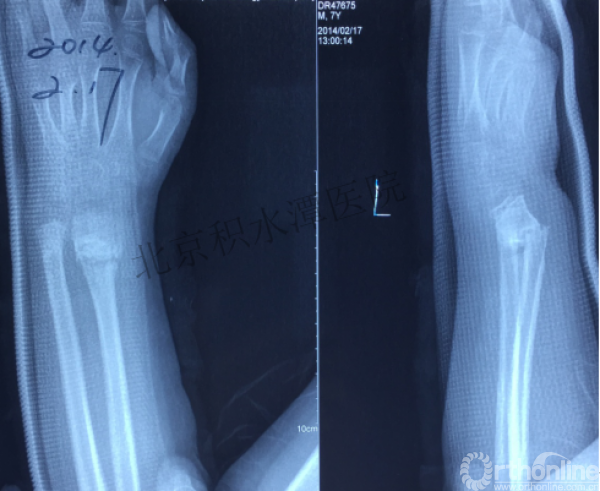

病例分享三

男孩、9岁,滑雪受伤,胫腓骨螺旋形骨折(粉碎性)

这个病例郭教授在积水潭医院骨科高研班时多次讲到,也在互动交流中惊人地看到,了解到现实之令人难以想象!

手法整复,石膏制动!

整复后7天

儿童具备强大的愈合潜力,同样也有极强的塑形能力